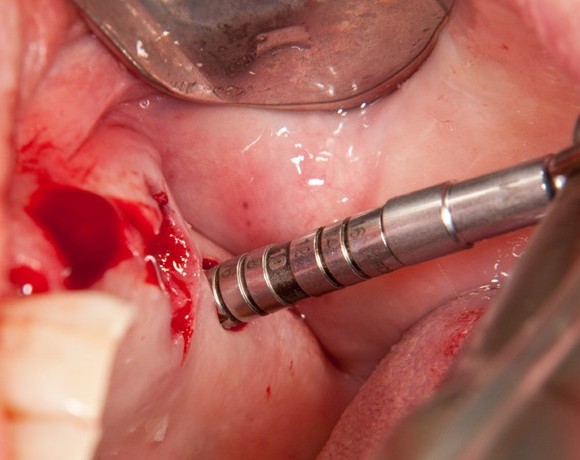

Bei dieser Patientin mussten die Zähne 22,26 und 27 aus parodontalen Gründen entfernt werden. Nach Extraktion der Zähne 22 und 26 wurden sofort in die Extraktionsalveolen die Implantate gesetzt. Zahn 27 war bereits sechs Monate zuvor extrahiert worden und die Knochenwunde gut ausgeheilt. Das geringe Knochenangebot wurde mit einem internen Sinuslift ausgeglichen. Im Bereich des Zahnes 23 wurde noch ein weiteres Implantat gesetzt. Da der Zahn 12 nicht angelegt und die Symetrie auf dieser Seite gestört war, wurden die Zähne 11 und 13 mit Teilkronen versorgt, um die Lücken zu schließen der Zahn 13 zu 12 umgebaut.